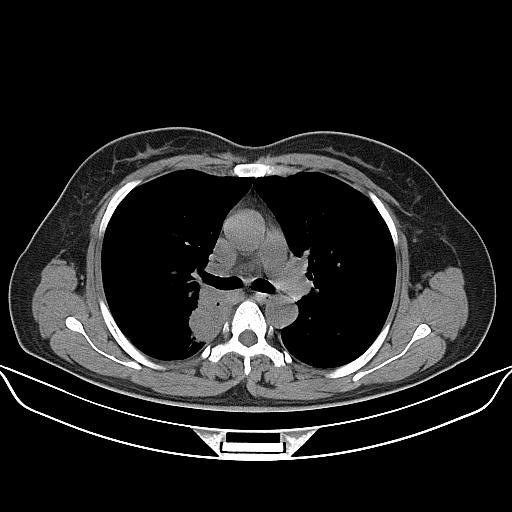

标题: CT22224:肺部肿块

f,48,主因咳嗽咳血来我院检查,无发热。

病灶边缘尚清,主体位于后下总膈,不除外神经源性肿瘤,建议行mri检查。

1)右肺下叶背段团块状软组织密度影;建议抗炎治疗后复查排除肿瘤性病变。2)右侧少量胸腔积液。

胸膜下脂肪影存在,考虑炎性假瘤,建议治疗后复查.